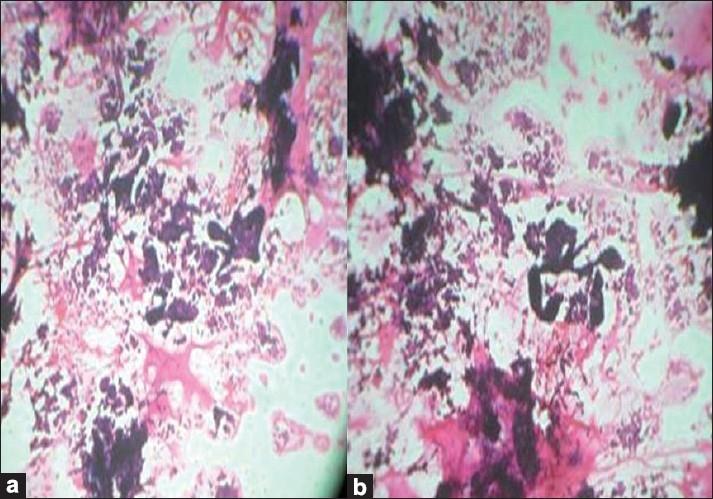

Colloid carcinoma (pure mucinous carcinoma) is an uncommon variant of breast carcinoma with distinctive cytological and histological features. These tumors are characterised by islands of tumor cells floating in a sea of abundant extracellular mucin. We present the cytology of two cases of colloid carcinoma occurring in 80-year-old and 45-year-old females. The fine-needle aspiration cytology helps to subcategorize the tumor type, thereby enhancing the knowledge about the distinctive cytological features of special and uncommon variants of breast carcinoma, their course and prognosis. A distinctive micropapillary variant of pure mucinous carcinoma which is rarely described, is represented in one of the cases. Also we report, here, colloid carcinoma in a female of reproductive age, a relatively uncommon occurrence.

摘要